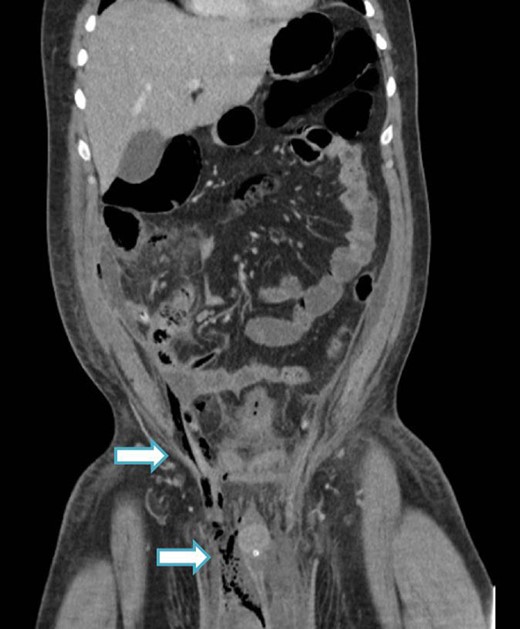

An urgent scrotal ultrasound demonstrated evidence of gas within the deep tissues of the scrotum but no abscess as shown in Fig. 1. Subsequently an abdomino-pelvic CT scan revealed multi-loculated collections in the right iliac fossa, suggesting perforated appendicitis with secondary extension of gas down the spermatic cord into the scrotum, as shown in Figs 2 and 3.

CT image (coronal slice) showing gas tracking from the right iliac fossa, down the spermatic cord into the scrotum.